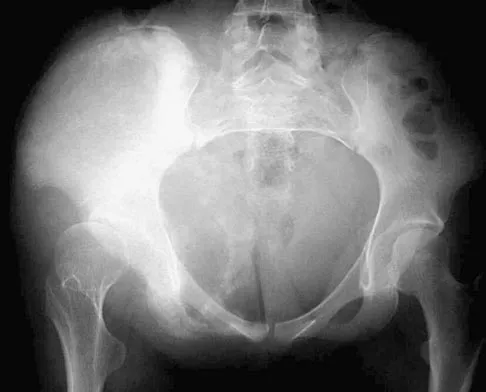

Figure 44 shows the radiograph of an 11-year-old girl who has hip pain. Further diagnostic workup should include

Explanation

The patient has severe acetabular protrusio, a condition that is frequently associated with Marfan syndrome. An echocardiogram is necessary to rule out the most serious consequence of this syndrome, aortic root widening, which can lead to aortic valve dysfunction or fatal aortic rupture. An electromyogram may be indicated for Charcot-Marie-Tooth disease, which is associated with acetabular dysplasia, but not protrusio. The renal ultrasound, the MRI scan, and the biopsy would be of no value in this patient. Protrusio can also be seen in patients with osteogenesis imperfecta and juvenile rheumatoid arthritis. Steel HH: Protrusio acetabuli: Its occurrence in the completely expressed Marfan syndrome and its musculoskeletal component and a procedure to arrest the course of protrusion in the growing pelvis. J Pediatr Orthop 1996;16:704-718.

References:

- Wenger DR, Ditkoff TJ, Herring JA, Mauldin DM: Protrusio acetabuli in Marfan's syndrome. Clin Orthop 1980;147:134-138.